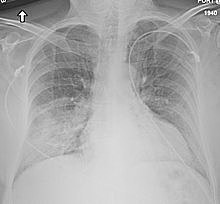

El síndrome respiratorio agudo grave es una neumonía atípica que apareció por primera vez en noviembre de 2002 en la provincia de Cantón, China. Ocasionó aproximadamente 770 muertes.